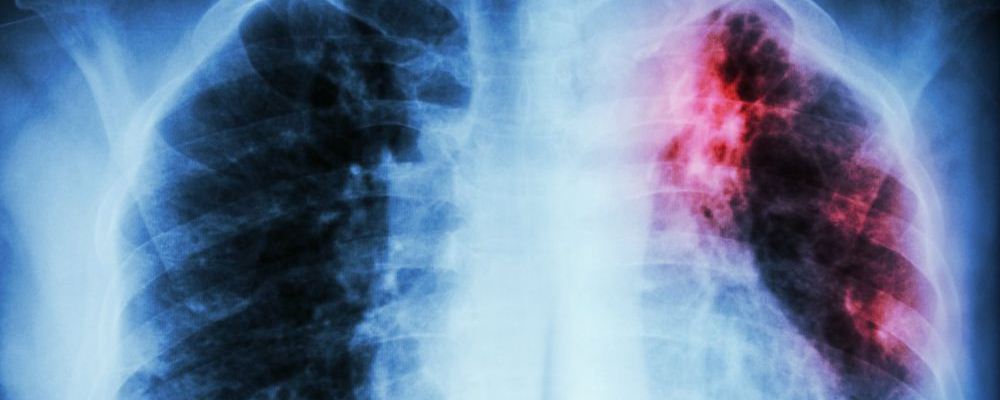

肺癌可是很可怕的疾病,其發(fā)病率和死亡率都很高,是一種威脅人的健康和生命的惡性腫瘤。早期發(fā)現(xiàn)問題治療恢復的可能性比較大,可是到了肺癌晚期的時候,就算就回來了也沒幾年好活了??墒?,最近湖南有個家庭發(fā)生了一件糟心的事情——12男孩患上原發(fā)性支氣管肺癌晚期疾病。這實在是令人震驚,這么小的年紀就得了這種病。

近日,湖南邵陽一名12歲男孩因鎖骨處長包塊,到醫(yī)院檢查,竟然得了原發(fā)性支氣管肺癌晚期!這種癌癥患病率和死亡率位居全球第一,但在未成年人中比較罕見。而造成此種疾病的原因,竟然是“懶,經(jīng)常熬夜,早餐基本上不吃!”